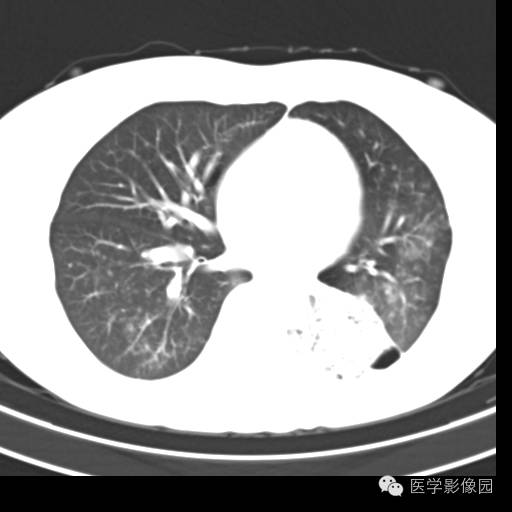

肺叶实变性支气管肺泡癌1例CT影像表现

【病例】肺叶实变性支气管肺泡癌1例CT影像表现